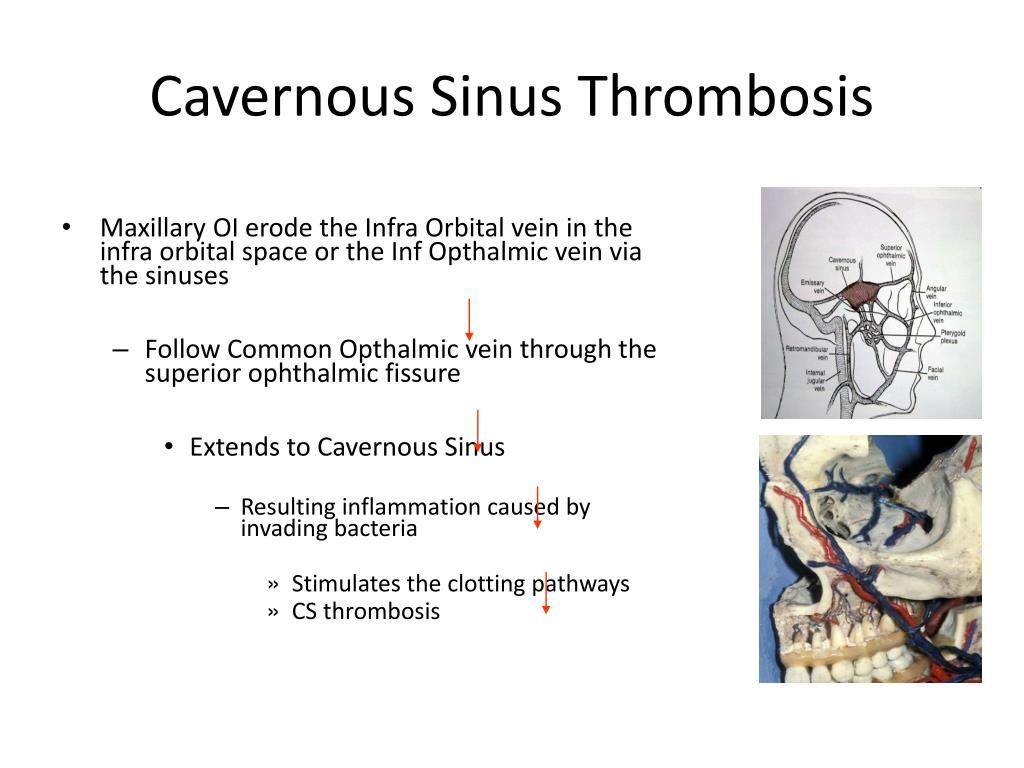

ترومبوز سینوس کاورنوس، که در اصطلاح پزشکی به آن Cavernous Sinus Thrombosis یا CST گفته میشود، یک وضعیت بالینی نادر اما بسیار جدی است که در آن لختهای از خون در سینوسهای کاورنوس تشکیل میشود. این سینوسها دو فضای وریدی مهم در قاعده جمجمه، در پشت هر دو چشم، هستند که وظیفه حیاتی جمعآوری خون کم اکسیژن از صورت، مغز و چشمها و هدایت آن به سمت قلب را بر عهده دارند. اختلال در عملکرد این سیستم حیاتی به دلیل تشکیل لخته خون، میتواند عواقب جبرانناپذیری به دنبال داشته باشد، چرا که فشار خون در رگهای مغزی و چشمی به شدت افزایش مییابد و به ساختارهای عصبی و عروقی مهمی که از این منطقه عبور میکنند، آسیب میرساند. این بیماری غالباً در نتیجه گسترش عفونت از نواحی مجاور به وجود میآید.

ترومبوز سینوس کاورنوس اغلب در نتیجه گسترش یک عفونت باکتریایی از نواحی مجاور به سینوسها رخ میدهد. شایعترین باکتری عامل این بیماری، استافیلوکوکوس اورئوس است. این عفونتها میتوانند از منابع مختلفی منشأ بگیرند. شایعترین منابع عفونت عبارتند از سینوزیت حاد (به ویژه در سینوسهای اتموئید یا اسفنوئید)، عفونتهای دندانی و عفونتهای پوستی صورت مانند جوشها. به دلیل ویژگیهای خاص شبکه وریدی صورت که فاقد دریچههای وریدی است، عفونت میتواند به راحتی از طریق رگها به داخل جمجمه و سینوسهای کاورنوس گسترش یابد. علاوه بر عفونتها، برخی شرایط زمینهای نیز میتوانند خطر تشکیل لخته را افزایش دهند. این عوامل خطر شامل دیابت، بیماریهای انعقادی خون، ترومای سر، بارداری و استفاده از قرصهای ضدبارداری خوراکی هستند که همگی میتوانند استعداد بدن به لخته شدن خون را افزایش دهند.